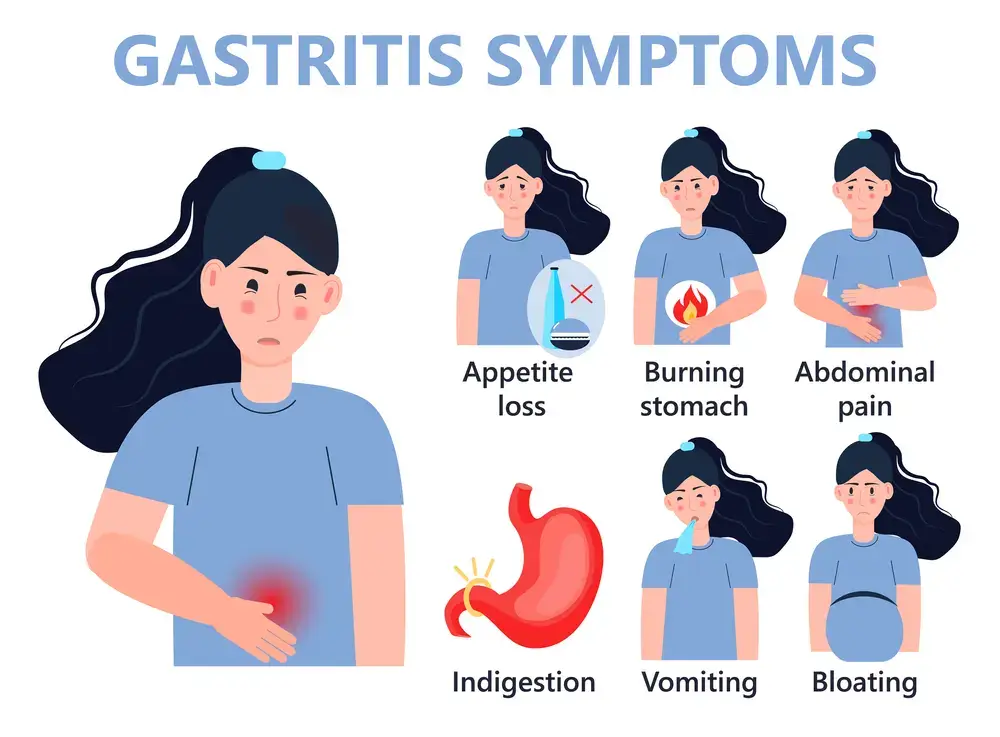

- Gastritis • Georgetown • Naturopath • Natural Health Clinic of Halton (March 19, 2017)

- Gastritis • Georgetown • Acupuncture • Natural Health Clinic of Halton (March 5, 2022)